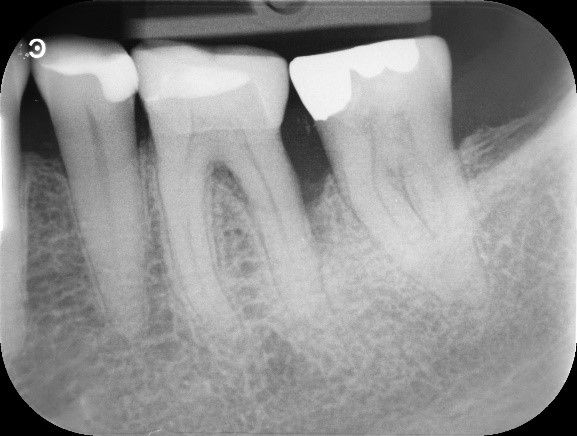

Die tiefe parodontale Tasche von 12 mm ist auf dem klinischen Bild zu erkennen, ebenso wie der intraossäre Defekt auf dem entsprechenden Röntgenbild.

Stabile klinische Situation zwei Jahre post OP mit einer Sondierungstiefe von 3 mm disto-bukkal bei 36. Das Röntgenbild belegt diesen Befund mit neu gebildetem Knochen an der einstigen Defektstelle.